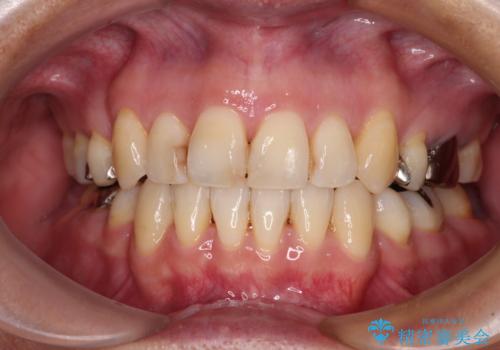

矯正歯科治療 → 上下顎前突(口ゴボ)

【モニター】治療途中で引っ越し ワイヤー装置を用いた抜歯矯正

目立たない装置で出っ歯を治したい ハーフリンガル矯正

内側に倒れた前歯と口元の突出感 ワイヤー装置での抜歯矯正

目立たない裏側矯正で突出感を改善 ハーフリンガル矯正

閉じにくい口元と八重歯 ワイヤー装置での抜歯矯正

前歯の隙間を閉じたい 口元も下げたい ハーフリンガルによる抜歯矯正

口元を下げてすっきりさせたい ワイヤー抜歯矯正で口元の改善

【モニター】口が閉じにくい 目立たないワイヤー装置で口元を引っ込める

隙間が空いて突出した前歯を治したい ワイヤー装置による抜歯矯正

ワイヤーによる抜歯矯正でガタガタの改善

唇を閉じやすく 出っ歯の抜歯矯正

八重歯と開咬を治したい 目立たないハーフリンガル矯正

出っ歯による口の閉じにくさを治したい ワイヤー装置を用いた抜歯矯正

前歯の出っ歯と口の閉じにくさが気になる 目立たないワイヤー装置での抜歯矯正

八重歯で口元が膨れている ワイヤー装置での抜歯矯正